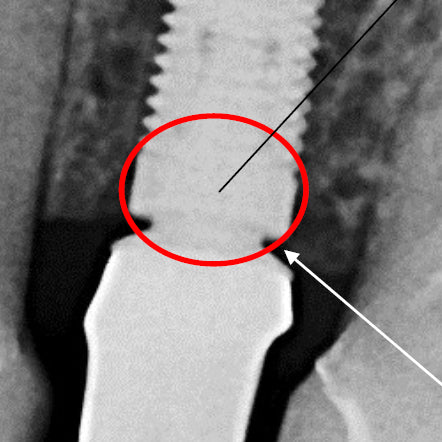

Proper Seating of an Implant One Abutment